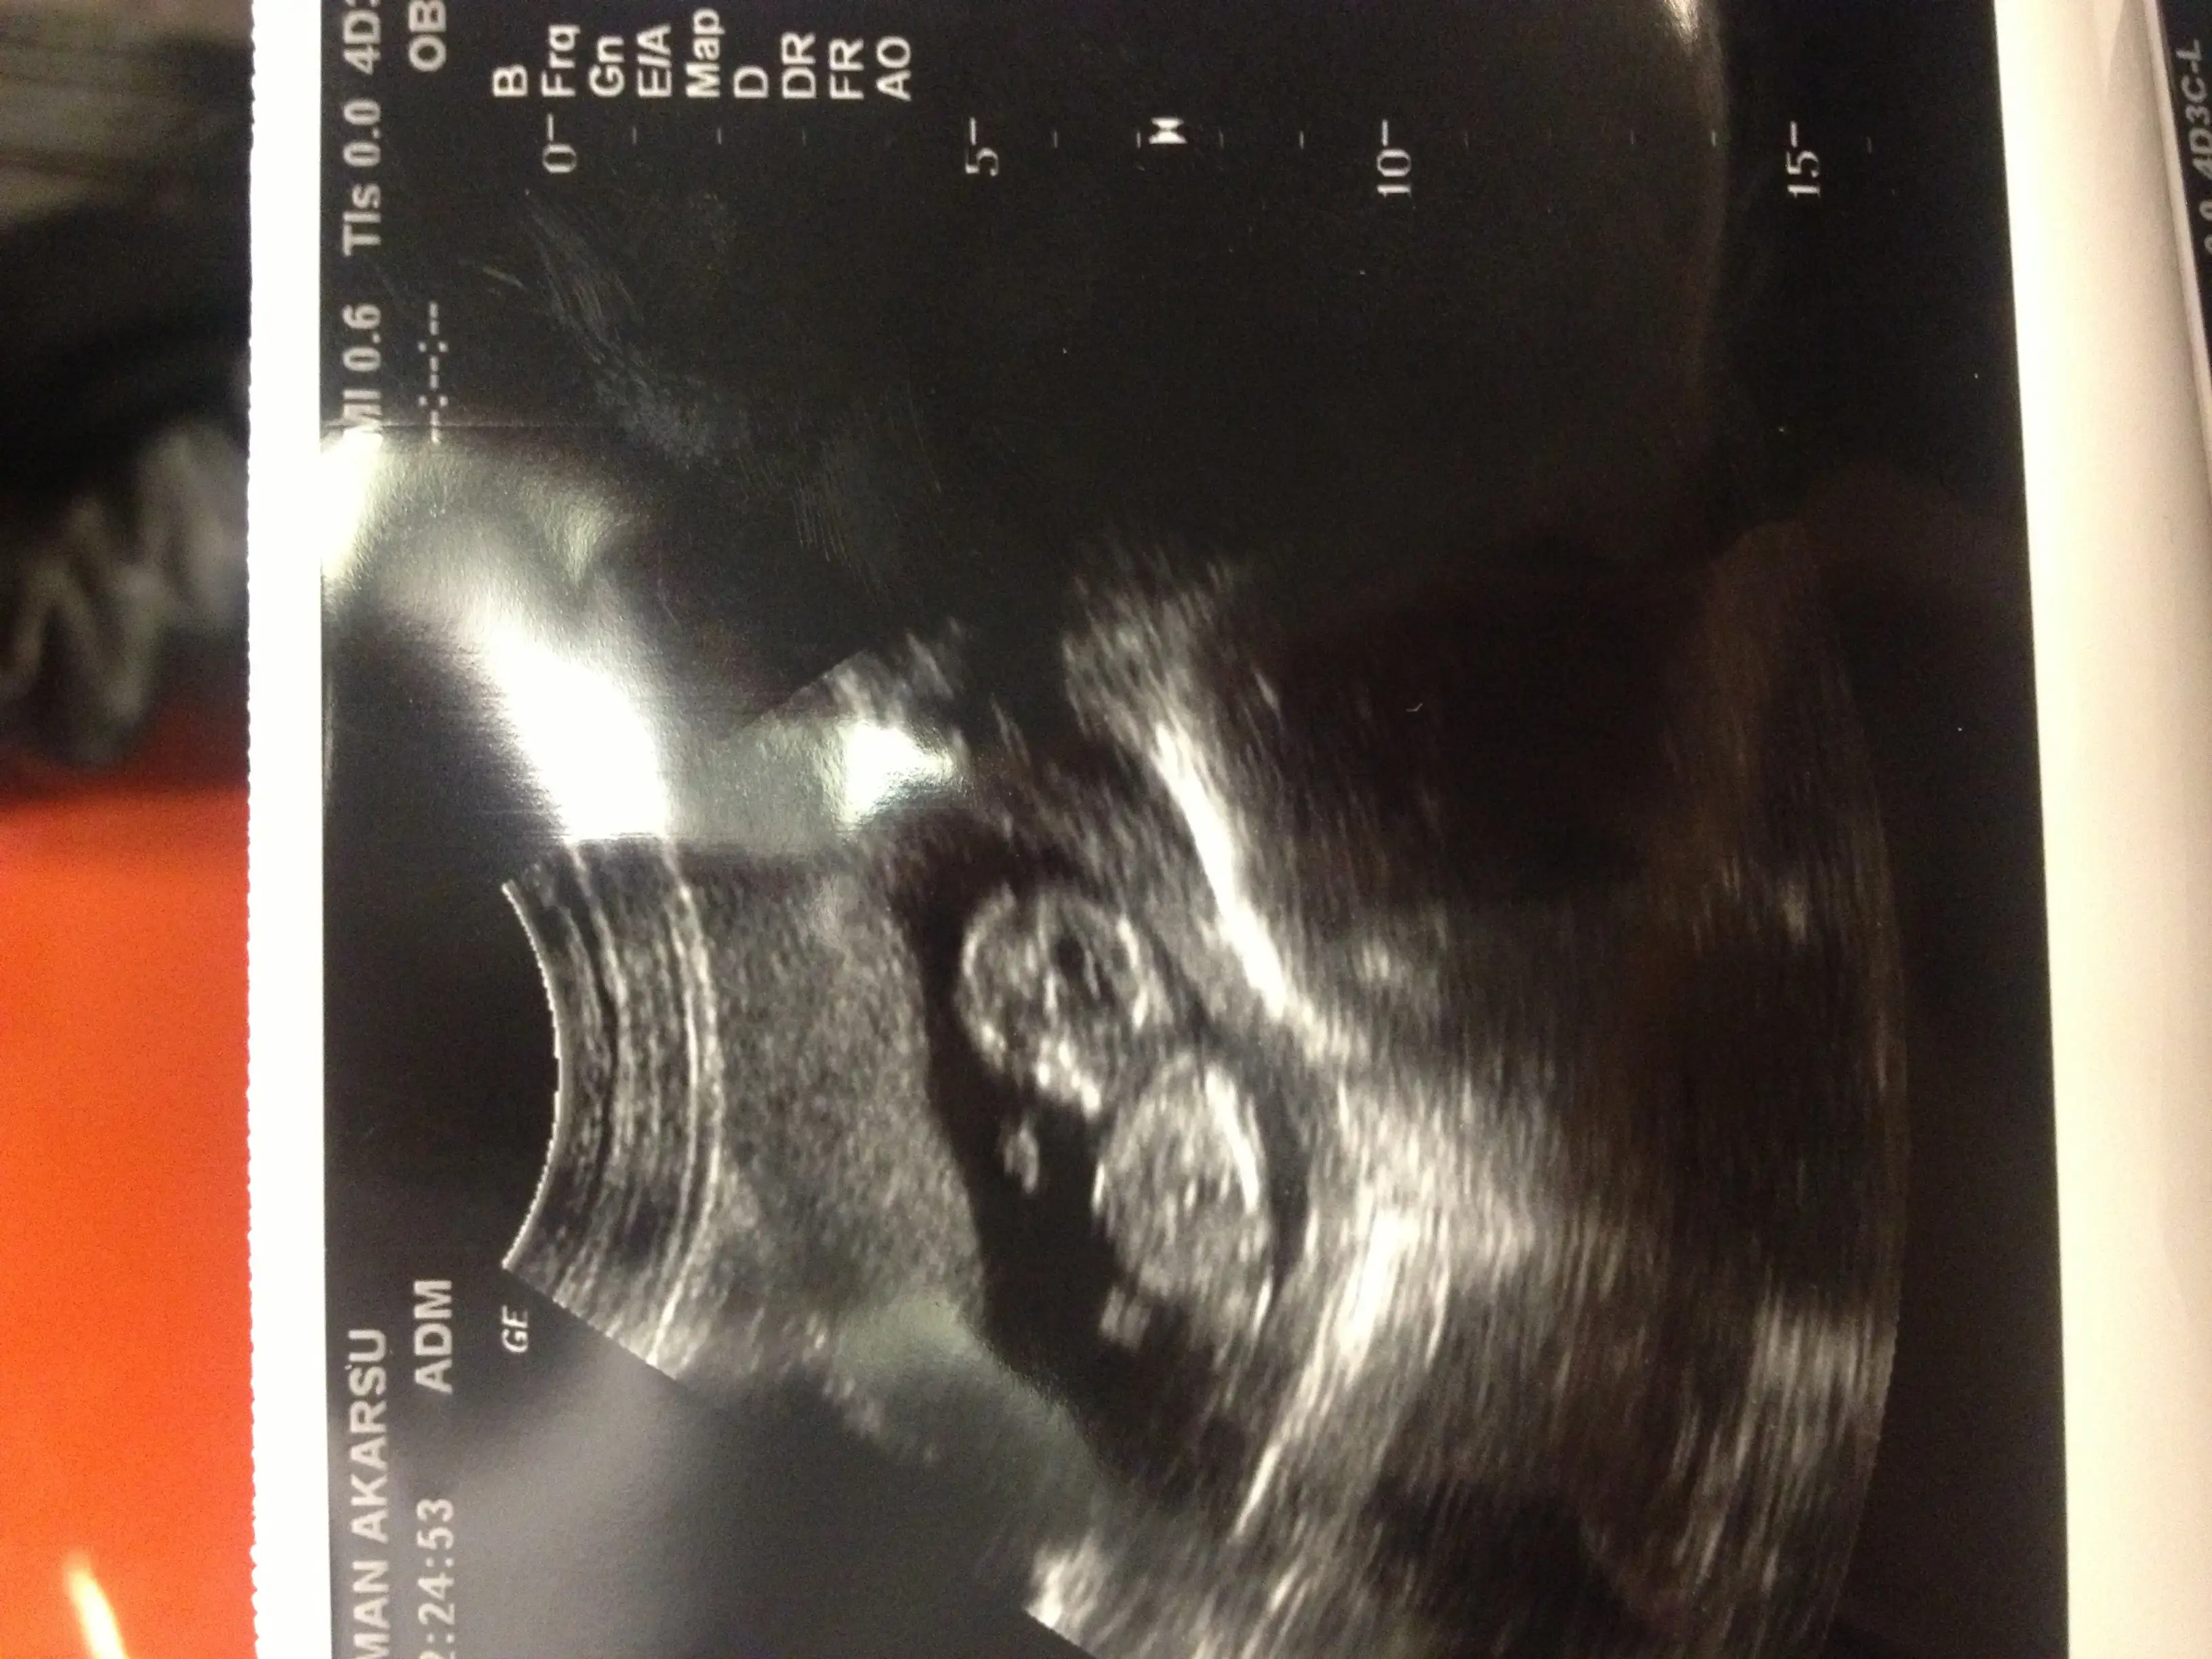

maşallah seninki ne güzel gelişmiş.bacakları falan ortada nub,mub kalmamış.direk cinsiyetini görmüştür doktor.erkek olabilir mi acaba bu kadar erken geliştiğine göre.merhabalaaarr...acaba bizim icin de bi thminde bulunabilir misiniz???? 12haftalık goruntumuz...

öyle mi? çok mu gelişmiş? 12 haftalık evet bacakları falan çok belirgindi çapraz yapmış yüzsütü uzanmıştı. doktor daha çok erkek tahmin için dedi...maşallah seninki ne güzel gelişmiş.bacakları falan ortada nub,mub kalmamış.direk cinsiyetini görmüştür doktor.erkek olabilir mi acaba bu kadar erken geliştiğine göre.

Sen kiza benzettim dedin bak simdiki resminemaşallah seninki ne güzel gelişmiş.bacakları falan ortada nub,mub kalmamış.direk cinsiyetini görmüştür doktor.erkek olabilir mi acaba bu kadar erken geliştiğine göre.